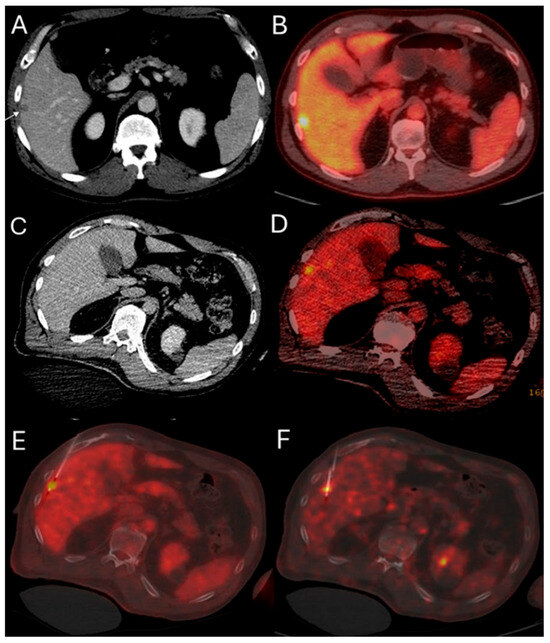

This method offers the significant advantage of allowing continuous visualization of PET-avid tumors through repeated, short breath-hold PET/CT acquisitions in real time, both prior to and during ablation. Real-time PET imaging is capable of detecting most CLMs, including lesions that may not be apparent on non-ceCT scans (Figure 2) [103]. The split-dose PET/CT technique enables precise intraprocedural localization and real-time visualization of the target tumor with electrodes in place, even following hydrodissection or tumor mobilization (Figure 3). This method overcomes the limitations of real-time ultrasound monitoring of the ablation zone, where visibility is often hindered by air produced during ablation. It also provides continuous visualization of the target tumor, enabling precise electrode repositioning to ensure that the ablation zone fully encompasses the tumor. Additionally, tumor viability can be assessed effectively using real-time split-dose FDG-PET [102]. The division of the two FDG doses accounts for the radioactive decay, so that approximately only 10% of the initial dose remains at the final post-ablation scan, which occurs hours after the first injection, thereby minimizing background activity from the original dose. The larger second FDG injection enables precise visualization of the ablation zone and increases sensitivity for detecting hypermetabolic activity from any residual viable tumor after ablation.

Figure 2.

51-year-old male with history of colorectal cancer undergoes MWA for new subcapsular liver metastasis in hepatic segment 5. Pre-ablation ceCT ((A) arrowhead) and FDG-PET/CT (B) demonstrate the tumor. The intraprocedural ceCT barely identifies the target tumor (C). Utilization of split-dose FDG PET/CT allows visualization, targeting, and monitoring of the FDG-avid tumor (D) with short acquisition 1 min breath-hold real-time scans allowing for accurate targeting for biopsy (E) and microwave ablation (F).